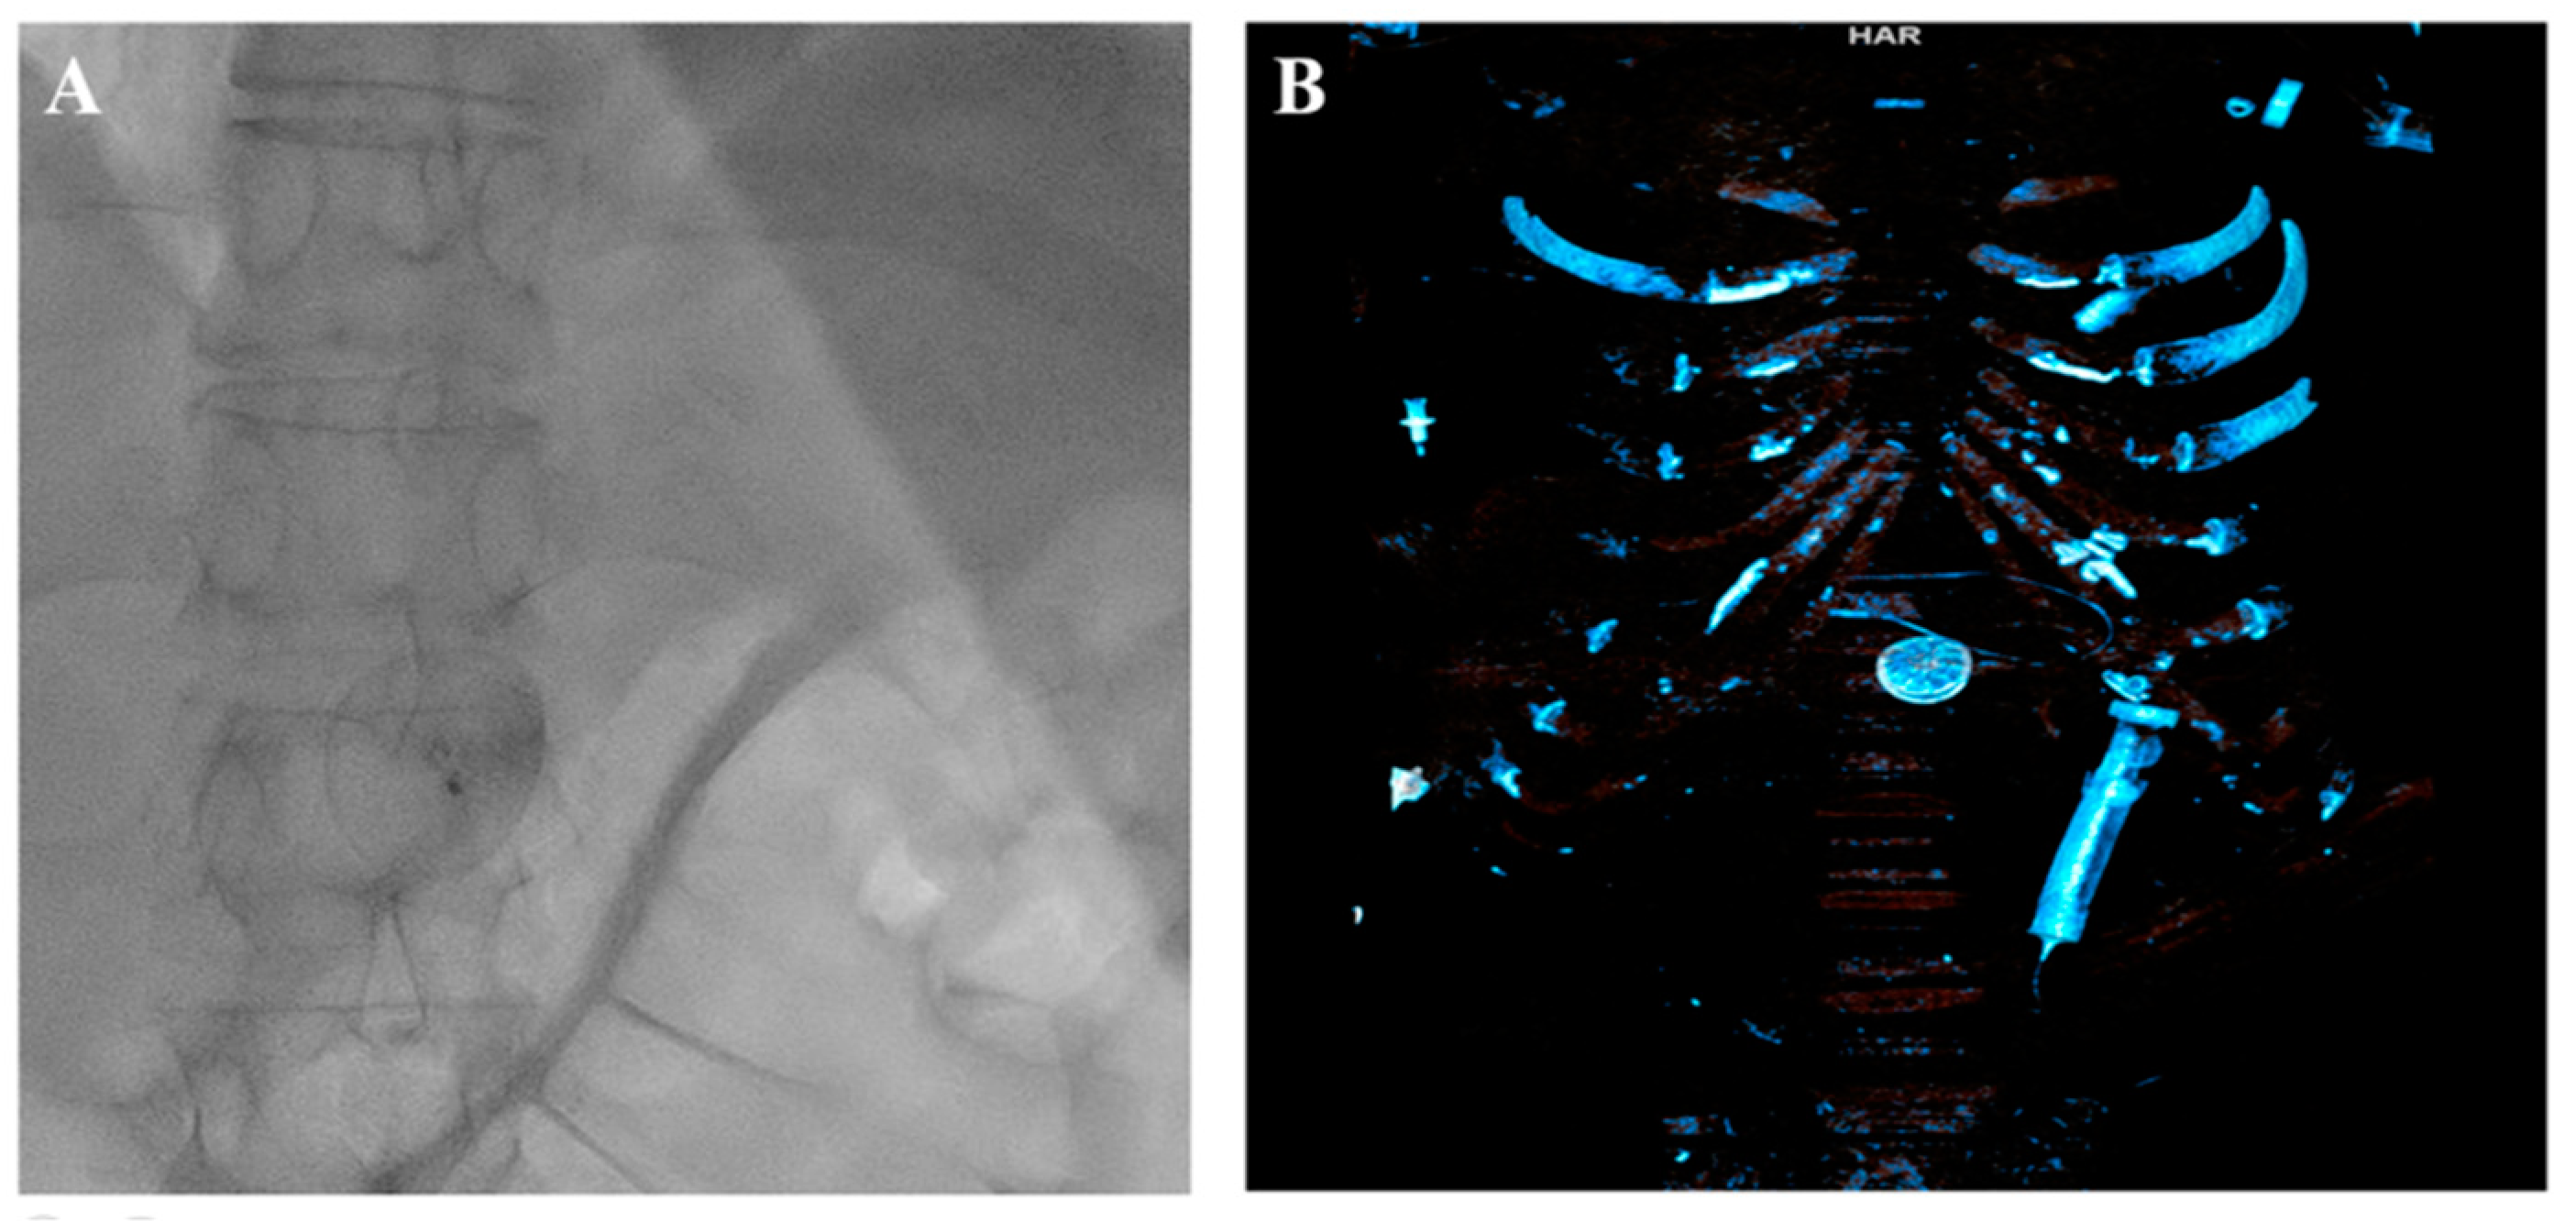

The attempts to snare it from the LA and LV were unsuccessful. Furthermore, the device promptly migrated to the abdominal aorta, located below the diaphragm at the junction of the truncus coeliacus, which was confirmed via a CT scan (Figure 4).

Figure 4.

Occluder in the abdominal aorta. (A) Fluoroscopy. (B) Computed tomography.